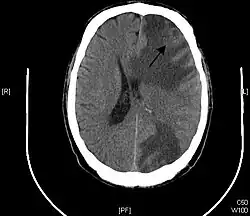

Brain - CT scan - Metastatic Pulmonary Adenocarcinoma. Arrow points to extensive edema of frontal lobe due to 23mm mass. Second area of edema can be seen in the left parietal-occipital region. - Genitourinary tract cancers, 11%

Brain imaging (neuroimaging such as CT or MRI) is needed to determine the presence of brain metastases.[6] In particular, contrast-enhanced MRI is the best method of diagnosing brain metastases, although primary detection may be done using CT.[10] Positron emission tomography (PET) is usually not considered suitable for imaging of brain metastases, because the most frequently used PET-radiotracer, 18F-FDG, does not only accumulate in the tumor but is naturally taken up by normal brain tissue, usually resulting in insufficient tumor-to-background contrast. PET-imaging of brain metastases is however feasible using alternative radiotracers, such as the Gallium-68 labeled peptide 68Ga-Trivehexin,[13] a tracer targeting the tumor cell surface protein αvβ6-integrin. 68Ga-Trivehexin demonstrated high uptake in a brain metastasis of tonsil carcinoma but no uptake in the surrounding healthy brain tissue, enabling a delineation of the brain metastasis (see image).[14]